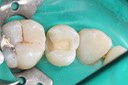

Kyle Chock #15 pre-op

Kyle Chock #15 caries removal

Kyle Chock #15 prep